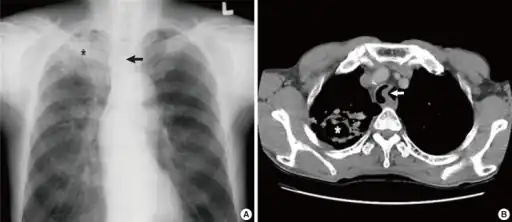

a)Image reveals tuberculosis asterisk b) CT scan of the chest shows tuberculosis with cavitation asterisk

a)Image reveals tuberculosis asterisk b) CT scan of the chest shows tuberculosis with cavitation asterisk Commensals vs pathogenic bacteria in COPD